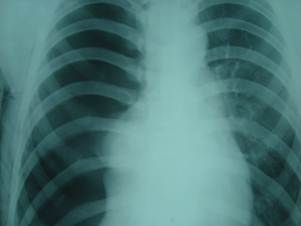

Какой патологический процесс в легких вы видите на данной рентгенограмме?

A) пневмония правого легкого

B) пневмоторакс правого легкого

C) эмфизема правого легкого

D) ателектаз правого легкого

E)цирроз правого легкого

{Правильный ответ}= B